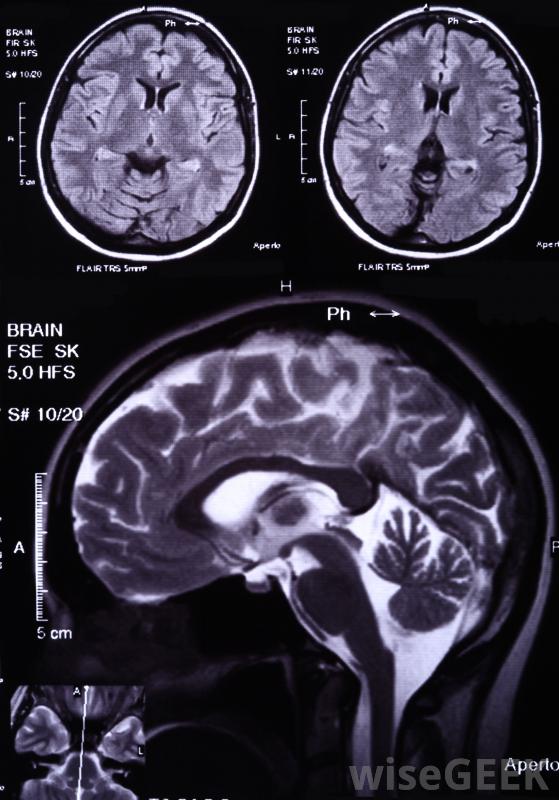

復發性膠質母細胞瘤的治療方法是什么(the Treatment for Recurrent Glioblastoma)?

腦中最常見的腫瘤,膠質母細胞瘤,影響腦的支持細胞。復發性膠質母細胞瘤是由于腫瘤在治療后發展而成,有時發生在遠離原發灶的區域。這種腫瘤的大多數治療方法試圖控制腫瘤的復發,這種腫瘤可能發生在多個部位化療包括將各種化學物質引入體內以殺死癌細胞復發性膠質母細胞瘤的治療通常需要手術,只要有可能,醫生通常會盡可能多地切除腫瘤,以防止腫瘤以后再次出現。有時,醫生會選擇放射外科手術,而不是侵入性手術,當聚焦射線直射腫瘤部位時,如果不同部位有多個腫瘤,放射外科手術通常是一種危害較小的選擇,所需的治愈時間要少得多。化療可能有助于治療復發性膠質母細胞瘤。放射治療通常是這種類型的膠質母細胞瘤的下一個輔助療法。靶向放療通常被使用,但這不是與放射外科一樣,研究還沒有表明將整個大腦暴露在輻射下能顯著提高存活率然而,當輻射被用來攻擊手術區域時,存活率增加了一倍多。這可能是由于放射能殺死任何未經手術切除的腫瘤細胞的結果。膠質母細胞瘤是一種腦癌化療使用強力藥物來攻擊癌細胞。許多類型的化療在本質上比手術更具全球性,使其成為治療復發性膠質母細胞瘤的有用工具。像替莫唑胺這樣的藥物經常被使用,因為它們會干擾腫瘤細胞~復制的能力。膠質母細胞瘤治療的第一步通常是腦部手術,然后是積極的治療還有一些靶向化療。貝伐單抗可以注射在腫瘤部位附近,它可以阻止腫瘤細胞產生血管,為腫瘤細胞提供營養。當與傳統的化療相結合時,貝伐單抗可以大大提高存活率。這種聯合療法還可以減輕腦腫脹,這減輕了需要服用其他藥物來控制這種癥狀。膠質母細胞瘤最常發生在45至70歲之間的成年人復發性膠質母細胞瘤會對周圍組織造成各種有害影響,包括癲癇發作和腫脹引起的頭痛。這種癌癥的患者通常必須采取其他藥物治療來避免這些影響。這些藥物包括抗驚厥藥和類固醇,可以減輕腫脹和緩解壓力就像大多數癌癥治療一樣,這些療法的結合通常能獲得最佳的生存機會,一些醫生將重點放在放射外科和化療來控制復發的膠質母細胞瘤上,這兩種療法都能迅速地治療多個腫瘤部位,一項研究發現,以這種方式聯合治療可以提高幾個月的生存率膠質母細胞瘤放射治療。